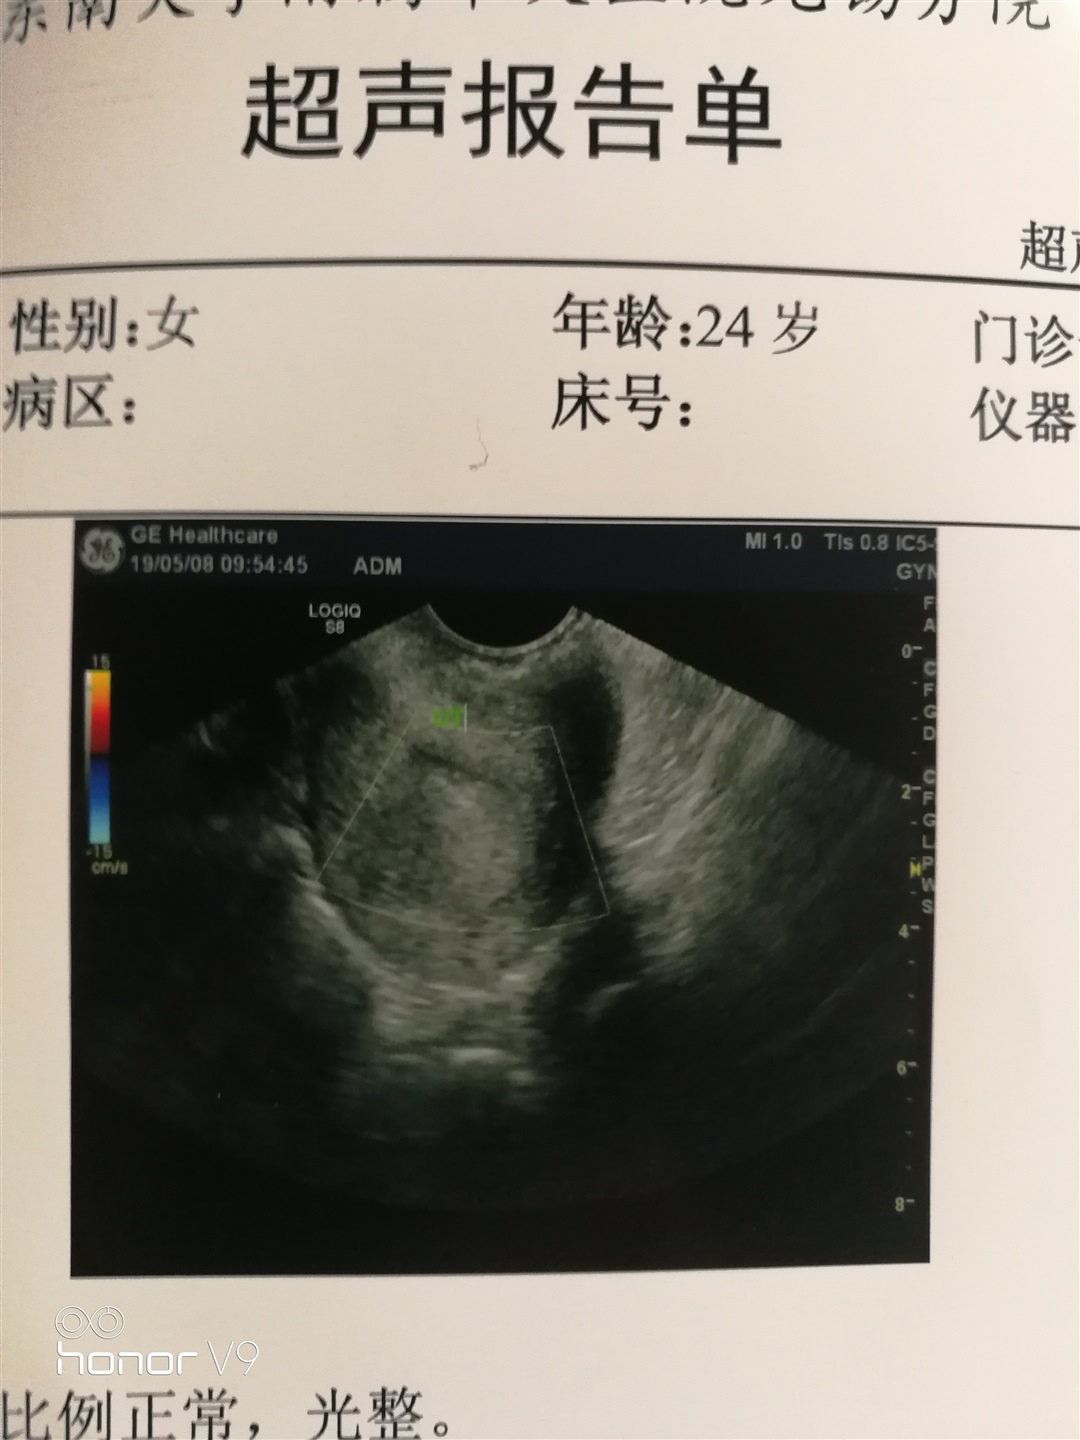

做的B超吗